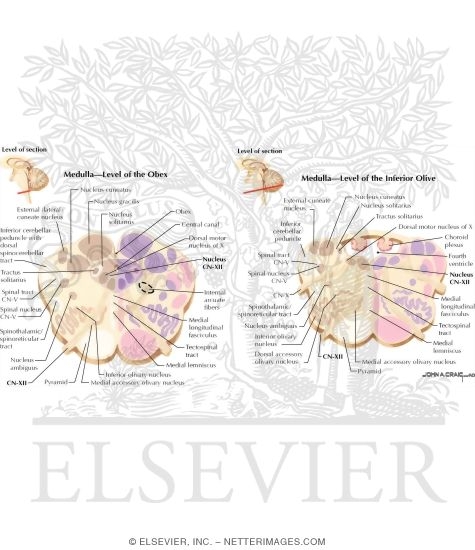

Hypoglossal Nerve Intermedullary Course

Hypoglossal Nerve Intermedullary Course